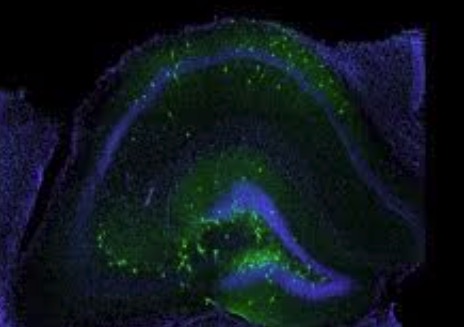

Ученые обнаружили, что мутации накапливаются в определенных некодирующих областях, связанных с набором белков, которые контролируют состояние включения/выключения генов. Ингибирование этих белков блокирует рост клеток рака простаты, показывая их ценность для разработки лекарственных препаратов нового поколения.

Было обнаружено, что около 21 000 кодирующих белок генов составляют около 2% всего нашего генома — план жизни или буклет с инструкциями по генетике человека. А остальные 98% генома составляют некодирующие области. Ученые пришли к выводу, что среди этой некодирующей ДНК скрыты важнейшие элементы, которые не только контролируют активность тысяч генов, но и играют важную роль во многих заболеваниях.

Геном человека невероятно сложен. Некодирующая область генома содержит миллионы генных переключателей, воздействующих на все клетки организма в разные моменты жизни.